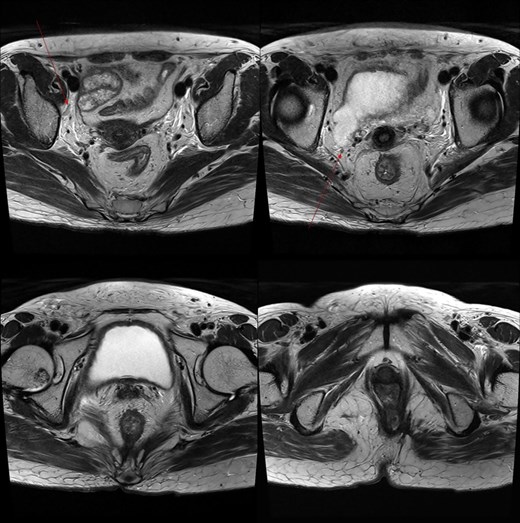

Pelvic MRI demonstrating the progression and extent of perineum and pelvic involvement. (A–C) Indeterminate lymph nodes in the bilateral external iliac chains, right obturator chain, and bilateral inguinal chains (thin arrow). (D) Presence of anorectal cancer with invasion of both levator muscles (thick arrow).